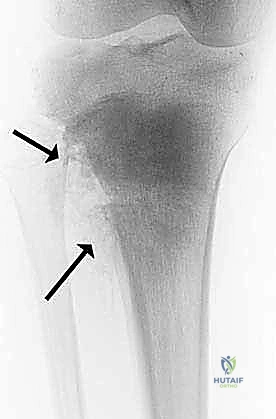

| الكسور المرضية (Pathological Fractures) | كسر يحدث في العظم نتيجة إصابة بسيطة جداً لا تسبب كسراً في العظم السليم (مثل التعثر الخفيف). يحدث لأن الورم أضعف بنية العظم. | طوارئ طبية |